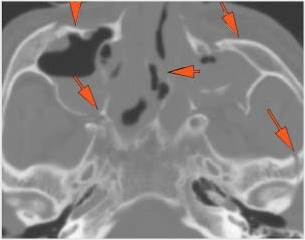

There is evidence of bony injury along the walls and/or floor of the orbit.

The supraorbital and infraorbital rims and orbital process of the zygoma and/or frontozygomatic suture are fractured.

The zygomatic arch is fractured.

There is entrapment of the muscles of mastication by fractures of the coronoid process and/or zygomatic arch.

There is bony injury of the body, alveolar ridge, premaxilla, the infraorbital rim, the palatine or the frontal process of the maxillary bones on either side.

The pterygoid processes of the sphenoid bone are fractured.